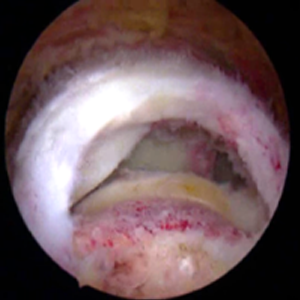

整形外科における手術の役割 肩腱板断裂治療のアルゴリズム 不全断裂 小断裂 中~大断裂 一次修復不能広汎性断裂 保存療法(リハビリ:運動療法/物理療法) 手術療法 関節鏡下腱板修復術 腱移行術、腱移植術、リバース型人工関節 腱板断裂の治療の基本は保存療法ですが、それが反応しない場合には、関節鏡下腱板修復術が適応されます。 修復前 修復後 関節鏡下腱板修復術は「肩に小さな穴を数か所開け、関節鏡で中をのぞきながら縫い合わせる方法」で、私の得意分野です。 不全断裂 小断裂 中~大断裂 一次修復不能広汎性断裂 保存療法(リハビリ:運動療法/物理療法) 手術療法 関節鏡下腱板修復術 腱移行術、腱移植術、リバース型人工関節 縫いきれないほどの大きな断裂には、腱の移植や人工関節が必要になります。 手術を望まない方へは、間葉系幹細胞を用いた再生医療の提供に取り組んでいます。